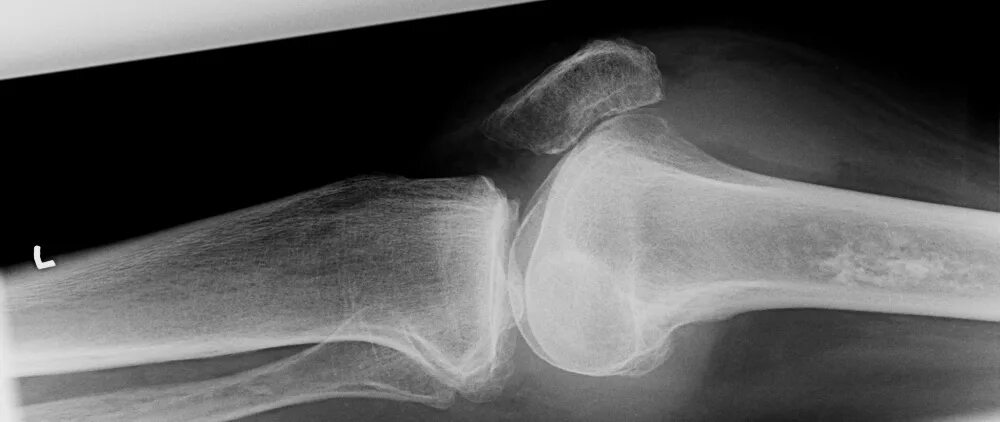

Снимок костей как называется